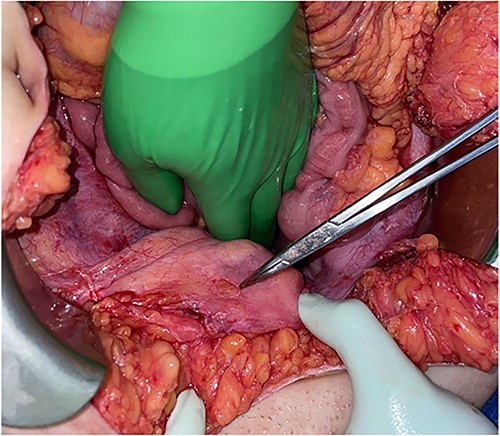

A blunt marking pen was identified in the right upper quadrant, lying on top of the omentum (Fig. 2). Inspection of the bladder revealed a 1-cm round defect in the dome of the bladder (Fig. 3). This was oversewn in two layers, with a subsequent negative leak test. The rest of the abdomen was inspected with no injuries identified to the colon, small bowel, uterus or ovaries. Lastly, the abdomen was washed out and closed. A Foley catheter was left in place and a drain was left by the area of bladder repair.

A marking pen was found within the mid-upper abdomen within the greater omentum in parallel to the transverse colon.